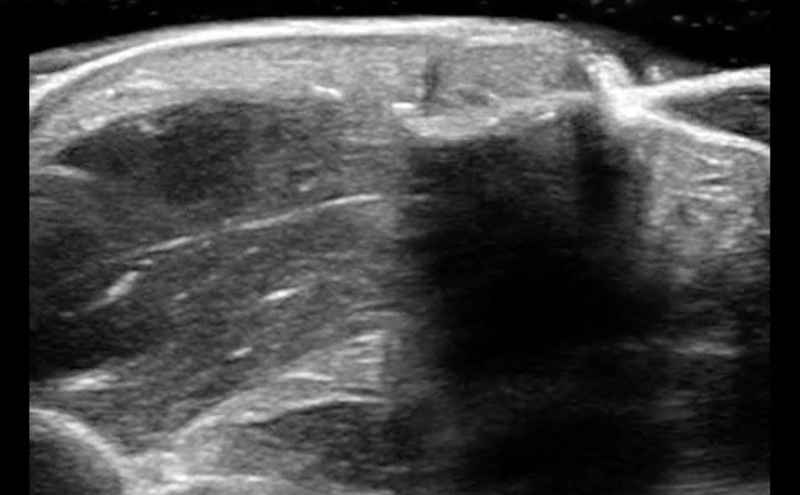

Abscess Evaluation